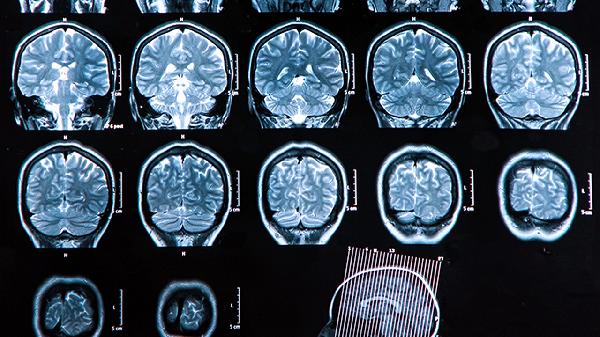

药物中的活血化瘀成分可扩张脑血管,增加缺血区域的血流灌注,缓解脑组织缺氧状态。这一作用对急性期脑血栓患者的神经功能恢复有帮助,但需结合影像学评估使用。